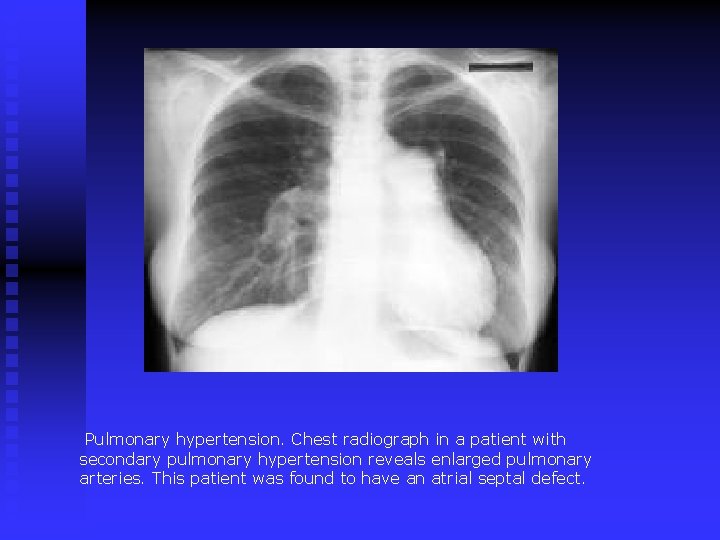

Chest X-ray Findings n central Pul arterial and/or RV enlargement , distal “pruning”

Pulmonary hypertension. Chest radiograph in a patient with secondary pulmonary hypertension reveals enlarged pulmonary arteries. This patient was found to have an atrial septal defect.